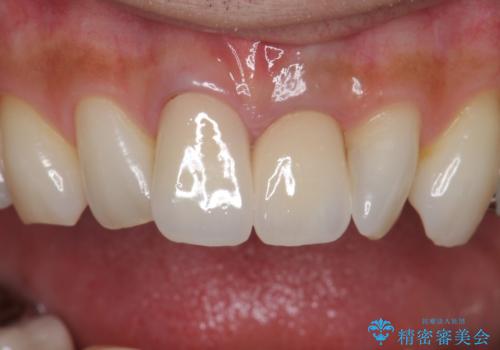

歯をある程度削ることにはなりますが、被せ物にすることで歯の変色を隠し短期間でキレイな口元に仕上げることができました。

前歯の色・形・ガタつきともに改善することができ、大変喜んでいただけました。